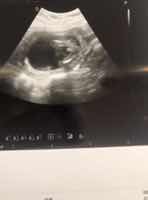

بنات شوفو سوناري..

ابوه يقول // ولدك شكله.. واصل حده ( م ق و م) 😅😅😂😂 جهزي عروسته🔞 ههههههههه